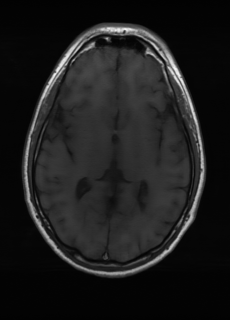

As we observe from the right image in Fig. 2, our BRM, both from MIMO and SISO settings, predicts the performance of dedicated models with a high correlation. We further choose the best three {λs}s=1Ssubscriptsuperscriptsubscript𝜆𝑠𝑆𝑠1\{\lambda_{s}\}^{S}_{s=1}, and perform the last stage of fine-tuning accordingly to (6). A visual evaluation on real data is shown in Fig. 3. For simulated data, please refer to the Supplemental Material section.

Base on the best performing {λs}s=1Ssubscriptsuperscriptsubscript𝜆𝑠𝑆𝑠1\{\lambda_{s}\}^{S}_{s=1}, we perceive that among T1subscript𝑇1T_{1}, T2subscript𝑇2T_{2}, and FLAIR, the results are best when T2subscript𝑇2T_{2} is sampled the most. We suggest that this makes intuitive sense as T2subscript𝑇2T_{2} images provide the best contrast out of the three sequences, which can compensate for the details lost in other images. The same observation can be made on the simulated data, where both T2subscript𝑇2T_{2} and FLAIR show good contrast. When the time setting is changed to non-uniformity, we can see that our search for the best sampling strategy reflects the change. T1subscript𝑇1T_{1} is sampled more as a result of faster acquisition time, while T2subscript𝑇2T_{2} is still sufficiently sampled.

Sequence LR SISO MIMO MIMO tuned GT

λT1=6.63subscript𝜆subscript𝑇16.63\lambda_{T_{1}}=6.63 Refer to caption (a) 34.38/0.9371 Refer to caption (b) 42.42/0.9883 Refer to caption (c) 44.60/0.9920 Refer to caption (d) 45.50/0.9940 Refer to caption (e) PSNR/SSIM

λT2=2.11subscript𝜆subscript𝑇22.11\lambda_{T_{2}}=2.11 Refer to caption (f) 29.74/0.8903 Refer to caption (g) 36.25/0.9734 Refer to caption (h) 36.42/0.9752 Refer to caption (i) 37.70/0.9832 Refer to caption (j) PSNR/SSIM

λflair=8.00subscript𝜆𝑓𝑙𝑎𝑖𝑟8.00\lambda_{flair}=8.00 Refer to caption (k) 39.89/0.9311 Refer to caption (l) 43.94/0.9864 Refer to caption (m) 44.74/0.9883 Refer to caption (n) 45.49/0.9894 Refer to caption (o) PSNR/SSIM

Figure 3: Visual comparison of different methods, with PSNR (dB) and SSIM values listed under the images. After recovery, the images are shaper with more visible details.